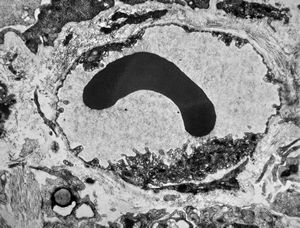

jejunumblood capillarz in lamina propria

venule in lamina propria